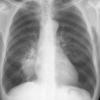

Case 1 Round pneumonia

Date: 04/16/2005

Views: 8072

Round pneumonia